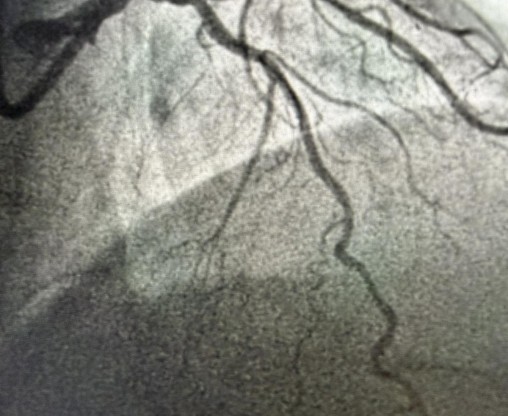

Tokom dva dana u angio sali izvedene su i izuzetno složene intervencije na koronarnim arterijama srca, uključujući perkutane intervencije na hronično - potpuno zapušenim krvnim sudovima srca i intervencije na tzv. glavnom stablu (left main) koja je glavna artrija srca i čije liječenje takođe spada u veoma rizične zahvate u interventnoj kardiologiji.

Kod pacijenta D.B iz Bratunca, koji je prije dvije godine prebolio infarkt i imao hroničnu potpunu zapušenost jedne arterije, urađena je perkutana koronarna intervencija kojom je arterija u potpunosti otvorena. Iako ove procedure imaju niži procenat uspjeha i zahtijevaju veliko iskustvo operatera, uspješno je izvedena. Dan nakon intervencije pacijent dobrog opšteg stanja otpušta se na kućno liječenje.

Još jedan slučaj koji izdvajamo kao posebno složen je bio kod pacijenta O.M (81), kod kojeg je dijagnostikovana teška trosudovna koronarna bolest.

„Pacijent je imao simptome angine pectoris. Nakon urađene koronarografije verifikovana je teška trosudovna koronarna bolest, gdje su bolesne bile desna koronarna arterija, dok je na lijevoj strani kritično mjesto bilo na glavnom stablu  odakle ide račvanje u dvije grane. Takvi pacijenti uglavnom završavaju na kardiohirurškom konzilijumu i na operaciji bajpasevima. Međutim, odluka konzilijuma u Banjaluci je bila da se, zbog godina života pacijenta,  radi perkutana intervencija na desnoj i lijevoj koronarnoj arteriji uključujući glavno stablo.Takve procedure zahtijevaju da se rade sa kontrolom imidžinga, savremene intravaskularne dijagnostike (IVUS), što smo mi i uradili. To dodatno povećava bezbijednost i preciznost zahvata. Procedura je trajala svega 45 minuta, a pacijent je već narednog dana otpušten kući“, izjavio je dr Janjičić.